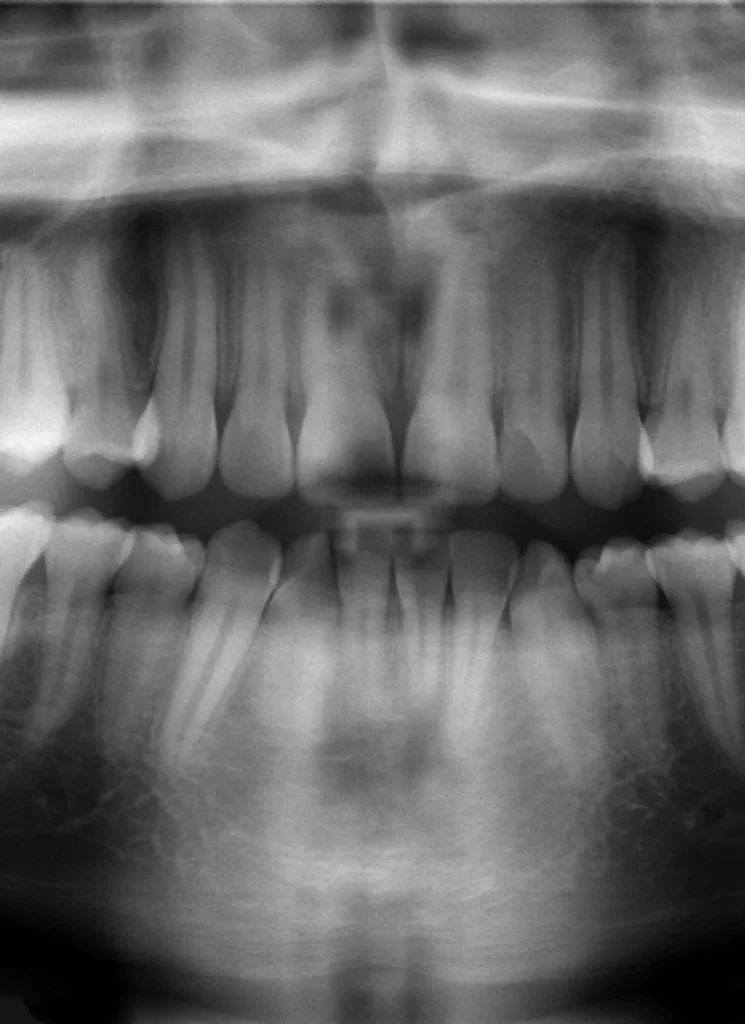

Utilisation de radiographies panoramiques

Si vous disposez de radiographies panoramiques dentaires récentes, leur analyse peut s’avérer particulièrement utile. Ces images offrent des informations précieuses sur votre santé bucco-dentaire, laquelle peut avoir des répercussions sur votre bien-être général. Elles constituent également un miroir de votre santé globale.